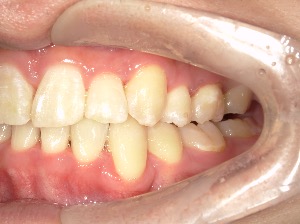

before

after

患者さんの年齢 20代 女性 症状 ガタガタを治したい 治療内容 マウスピース矯正治療 費用 90万(税抜) 治療期間・回数 治療期間2年、通院回数10回 メリット 笑顔が綺麗 デメリット・リスク 期間がかかることがある - マウスピース矯正